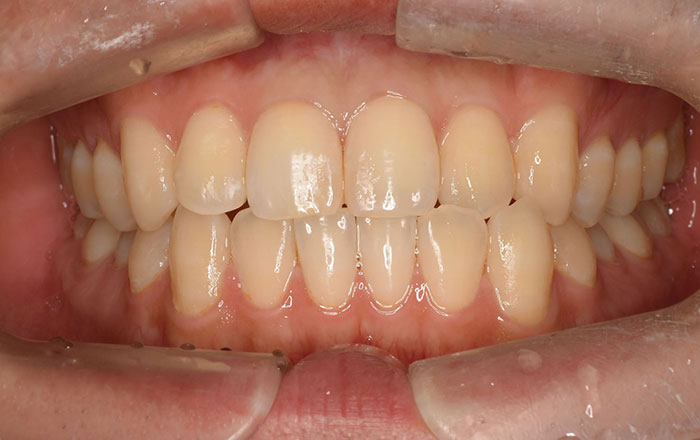

その場合は、当院では

1. ホワイトニング

2. ラミネートベニア

3. セラミッククラウン

の方法ご提案しています。